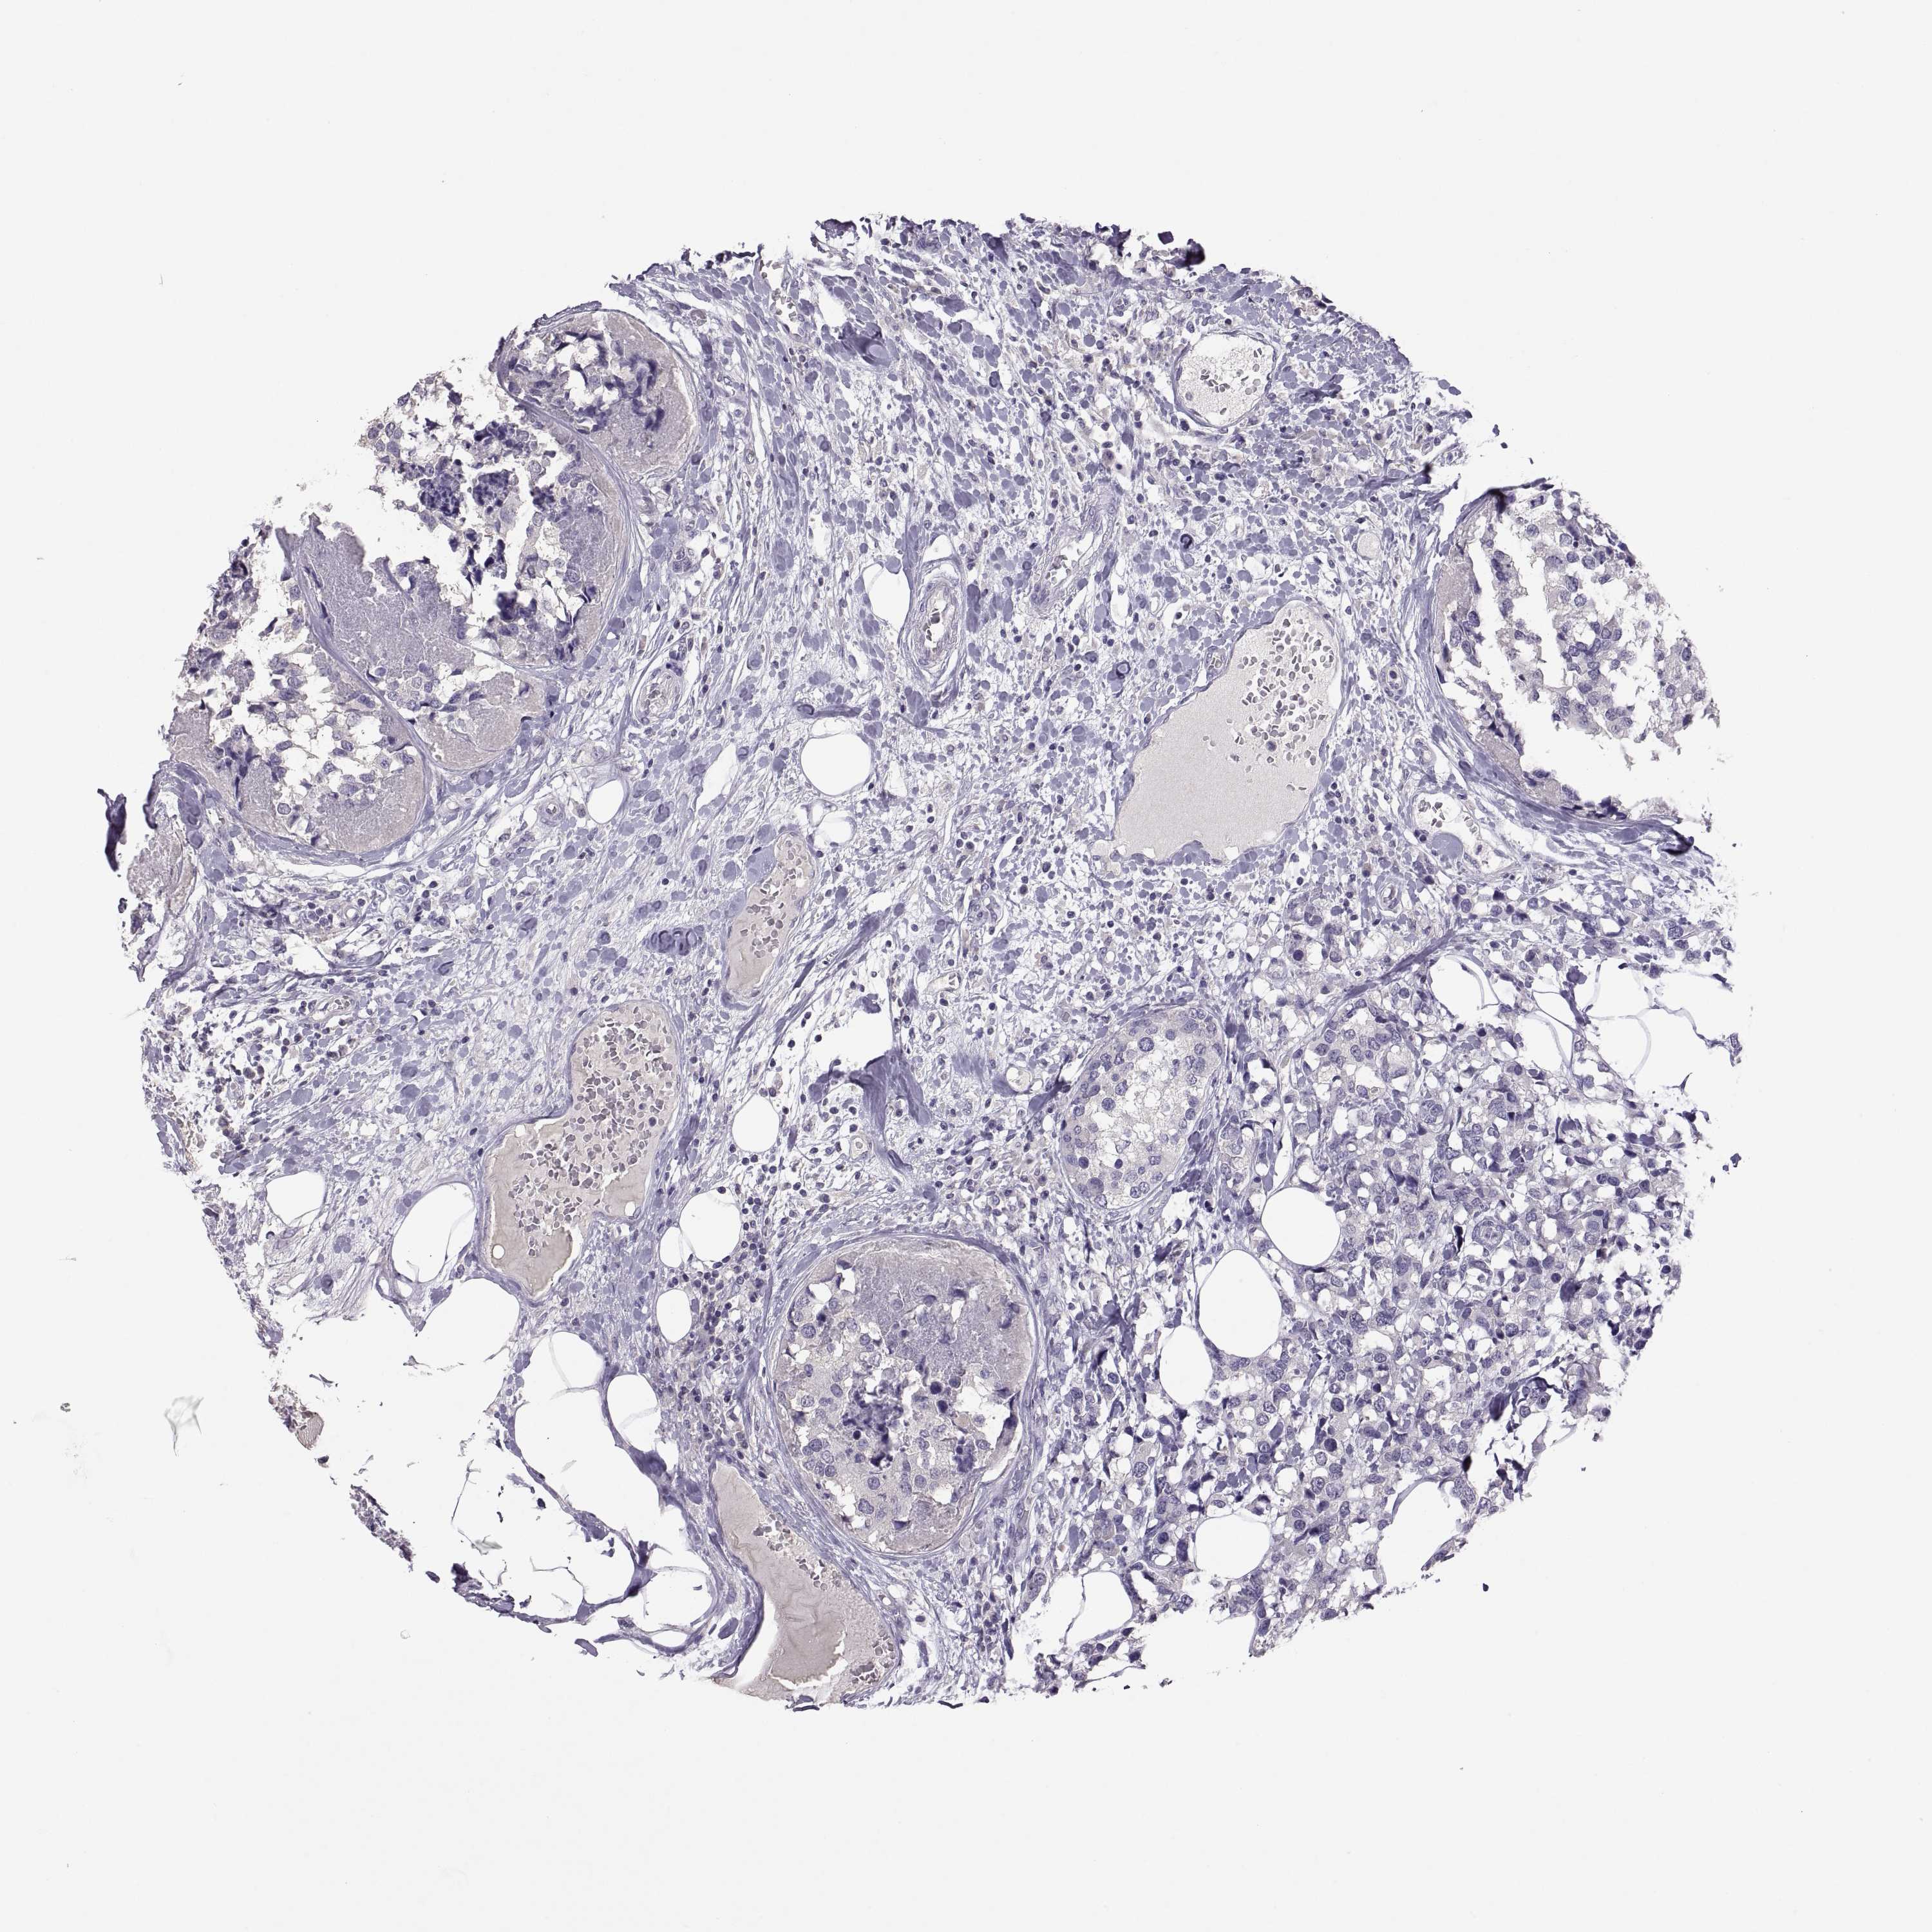

CANCER BREAST CANCER Show tissue menu

BRCA TCGA BRCA VALIDATION PROTEIN EXPRESSION

Breast cancer

Human cancer

Breast invasive carcinoma